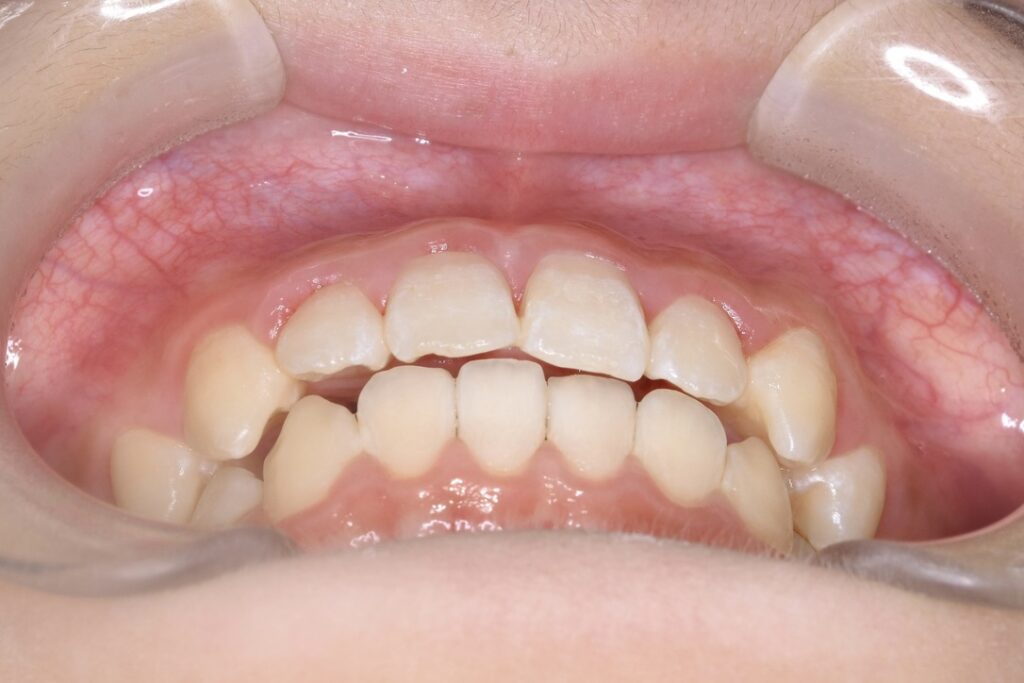

BEFORE

主訴 通っている歯医者で矯正した方がいいと言われて気になっている。下の前歯がでこぼこしている。

診断名・主な症状 下顎前歯の叢生を伴う過蓋咬合

治療内容 上下の歯並びの幅を拡げつつ、前歯の関係を改善しました。

使用装置 急速拡大装置

リンガルアーチ

機能的矯正装置(マイオブレース)

抜歯部位 抜歯なし

治療期間 2年 + 後戻り止め期間(3年 )

通院回数 20回

費用 50万円程度(税別)  29331